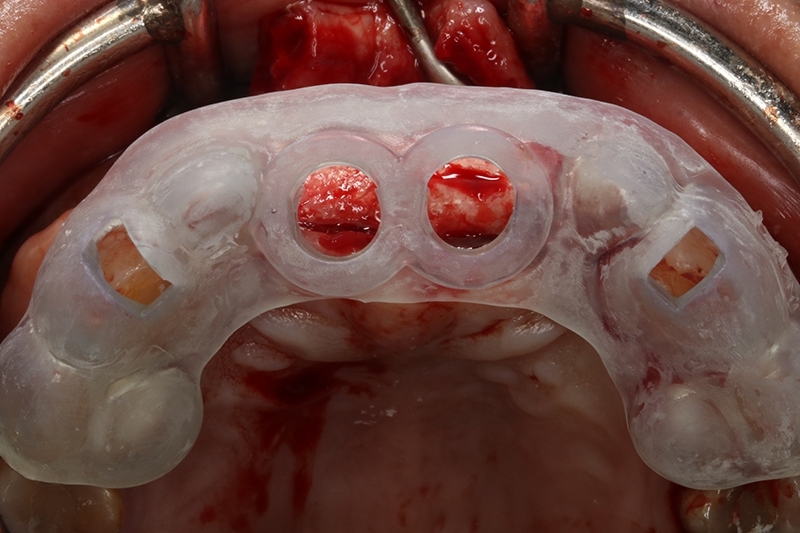

放置植牙數位導板

使用數位導板進行植牙

植體植入,置放於理想的水平與垂至高度位置

縫合傷口